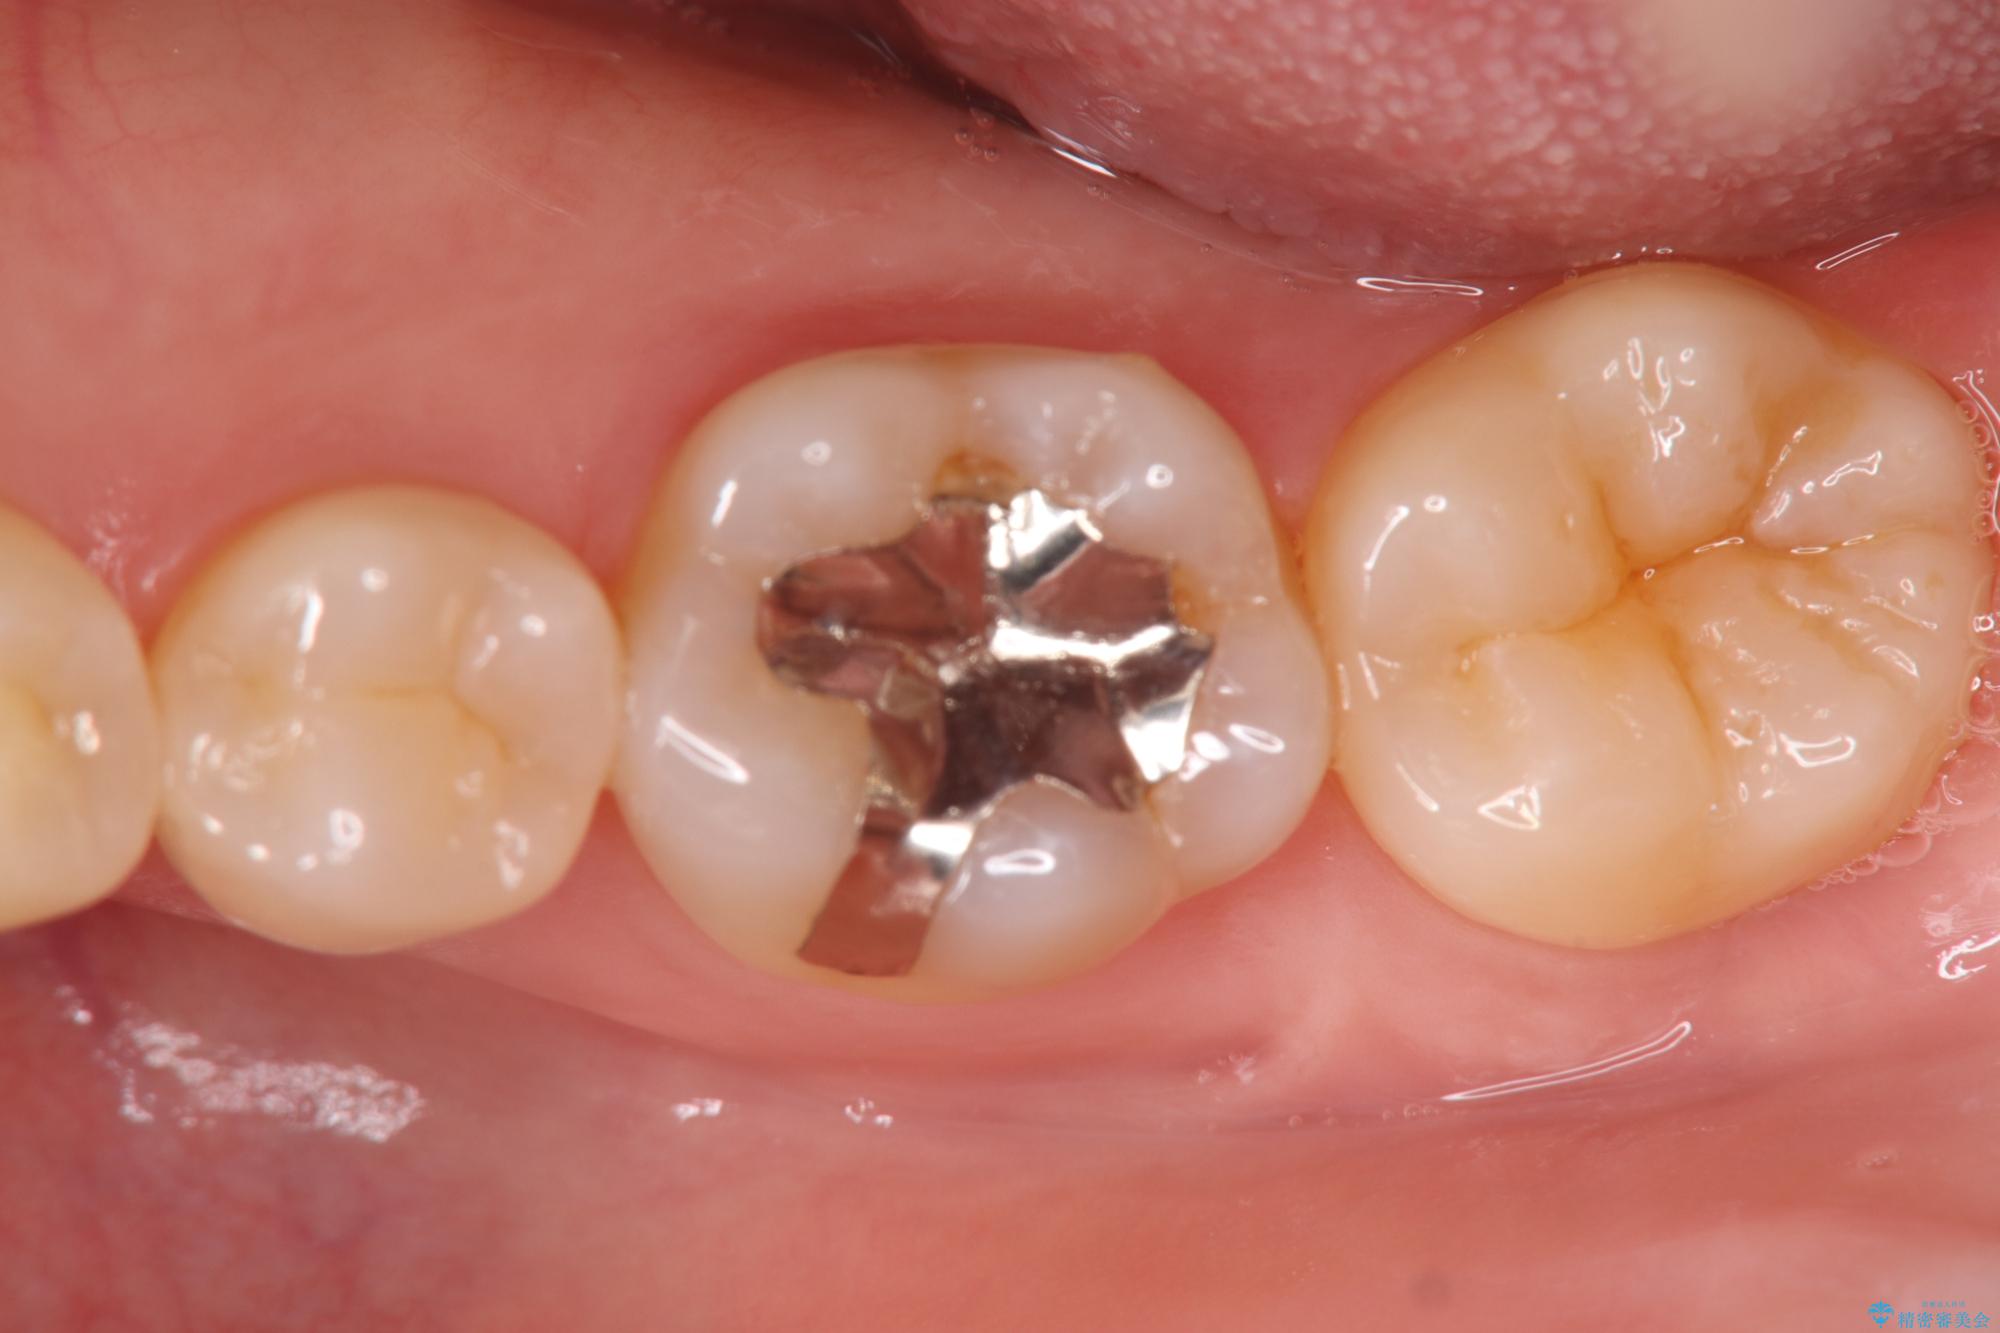

歯が欠けたことによるものか、もしくは以前装着された修復物の不適合が原因と考えられますが、銀歯(メタルインレー)と歯との間に大きな段差が認められ、汚れが溜まりやすい状態となっていました。

このような状態では、修復物の内部で虫歯が進行している可能性が高いため、治療が必要と判断しました。

今回は、経年的な劣化が少なく、汚れが付着しにくいセラミックインレーを用いて治療を行いました。